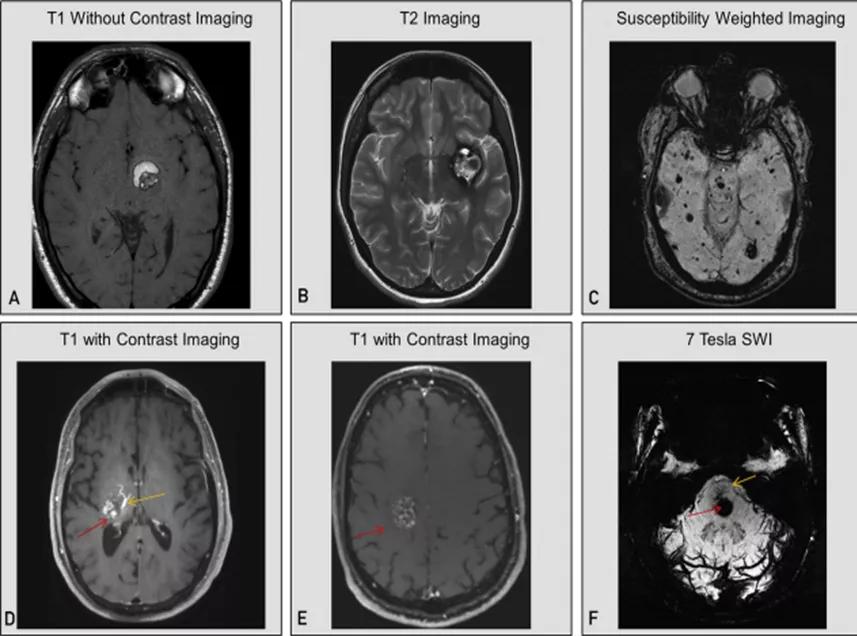

图5:颅内海绵状血管瘤在不同核磁序列中的表现特点:A为T1序列(非增强),提示近期出血的海绵状血管瘤;B为T2序列,提示陈旧性出血的海绵状血管瘤;C为SWI序列,提示家族型多发海绵状血管瘤;D为T1增强序列,提示合并发育性静脉异常的海绵状血管瘤;E为T1增强序列,提示海绵状血管瘤病灶轻度、斑片状强化特点;F为7T-SWI序列,提示合并发育性静脉畸形的海绵状血管瘤

T1加权序列可显示与近期亚急性出血有关的高信号(图5A),如果近期没有出血,病灶可能显示为等信号。T2加权序列中病变中央区一般呈网状,类似于桑葚,病变周围呈提示含铁血黄素环的低信号(图5B)。

含铁血黄素敏感序列,包括梯度回波序列或SWI,通过显示海绵状血管瘤部位的低信号并可能显示额外的海绵状血管瘤(图5C)来帮助确诊。无发育性静脉异常合并的多个海绵状血管瘤可能提示家族性,但也可能见于辐射诱发的患者当中。除了T1加权增强MRI之外,SWI可以帮助识别相关的发育性静脉异常(图5D)。

在增强序列中,海绵状血管瘤可能会呈弥漫性轻微强化(图5E),但不会明显强化或环形强化。后者如果伴有SWI序列的改变,则更多的是提示出血性转移瘤、感染性进程,或者很少是炎症/脱髓鞘性疾病。